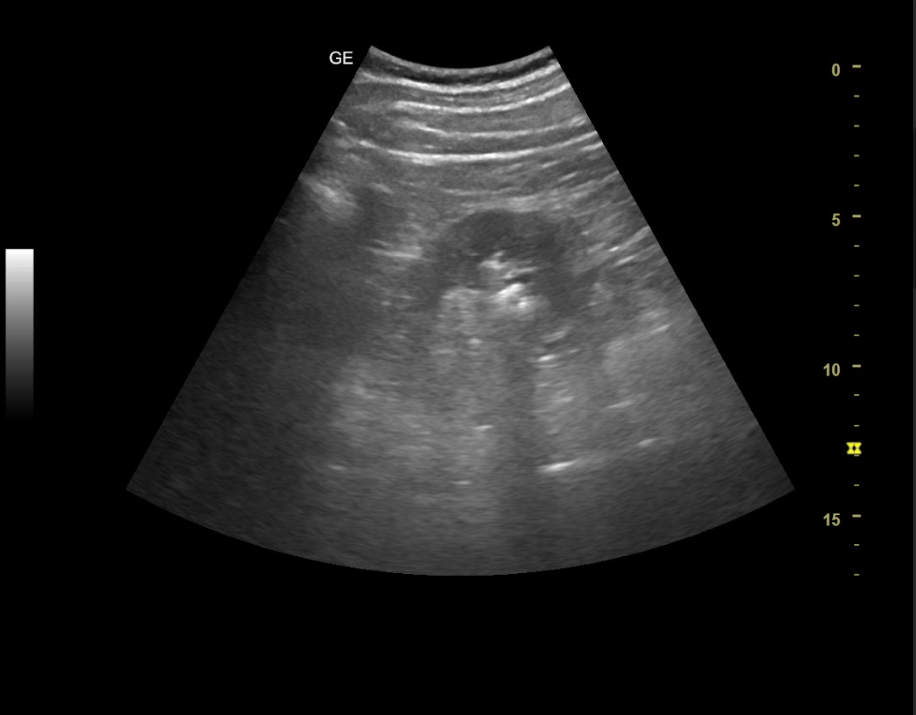

La auscultación cardio-respiratoria es anodina, a nivel abdominal presenta dolor a la palpación profunda en flanco derecho, irradiado a hipogastrio, sin defensa. Puño-percusión renal derecha positiva, izquierda negativa. Ante la elevada sospecha clínica de cólico nefrítico derecho, se decide realizar ecografía clínica para descartar hidronefrosis asociada al cuadro.

Hallazgos ecográficos

Ambos riñones son de tamaño similar considerándose normales y no apreciando hidronefrosis asociada. En el interior del riñón derecho se aprecia litiasis renal única que proyecta sombra posterior de diámetro máximo de 8,68 mm y potencial responsable del cuadro.